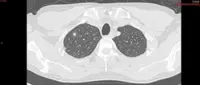

Meanwhile, Dr Anand said the best screening test is through low-dose computed tomography (LDCT) scans, which are widely available throughout the country and that currently, the target individuals for screening tests are smokers and former smokers within certain age groups.

LDCT is a single- breath high-resolution non-contrasted chest scan that requires no insertion of needles, blood test or prior fasting.